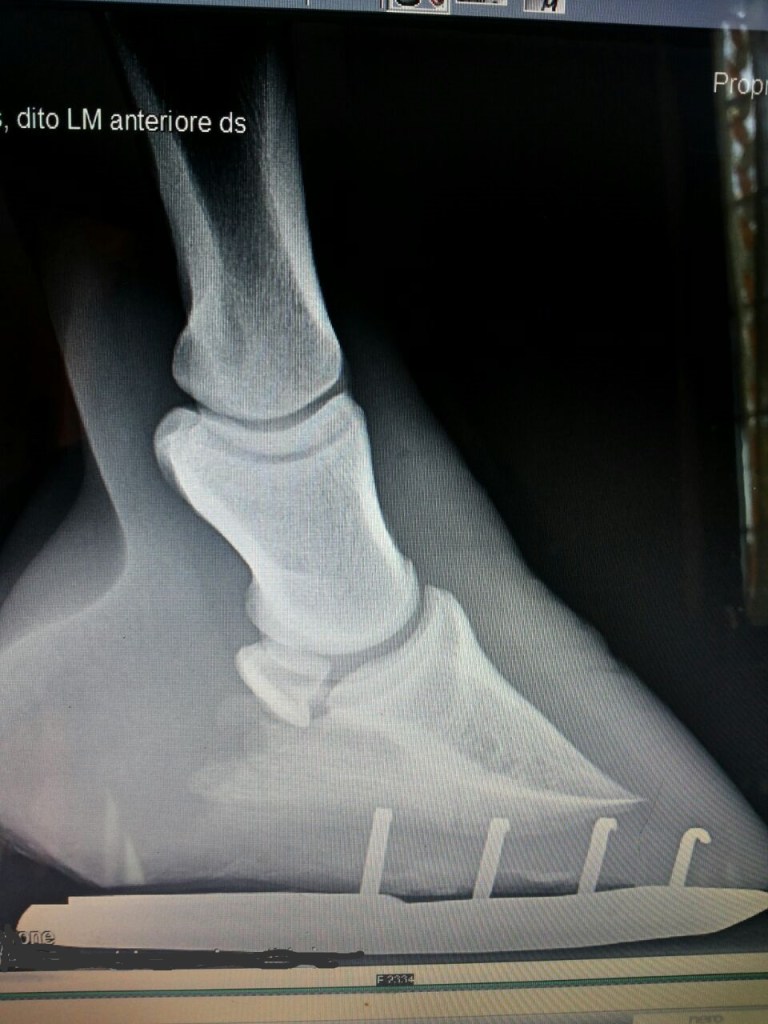

Il maniscalco, per quanto possa essere bravo e preparato, non può e non deve fare a meno della buona collaborazione con il veterinario. Ci vuole competenza ma anche umiltà. La ricerca scientifica sta facendo dei passi importanti riguardo ai cavalli sportivi e non, per questo motivo non si può operare individualmente. Spesso abbiamo bisogno di radiografie ed ecografie per conoscere meglio lo stato del piede equino nel suo interno e solo una accurata analisi ci mette in condizioni di operare con cognizione. La scuola militare di mascalcia era incorporata presso l’Accademia di veterinaria militare, gli insegnati di anatomia erano veterinari… un motivo ci sarà!

Piede ferrato con due barbette laterali e anti shock